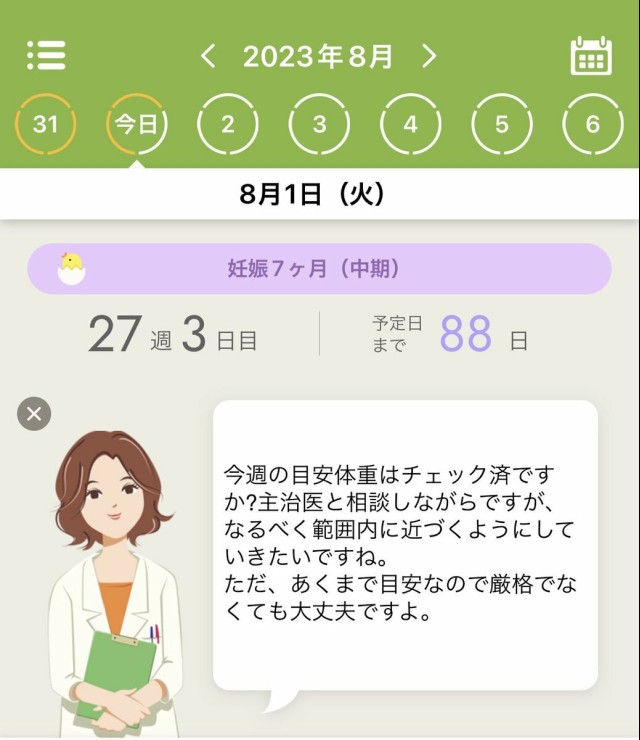

体重管理 ずっと体重横ばいだったのが前々回の健診で体重4週で一気に3kg増えて指導を受けて、前回は数百g増に留めた。非妊娠時に比べると3kg増はちょっと少なめ?らしい。一気に増えるのが良くないみたいだけど増えなさすぎも毎回アプリに怒られるのしんどい。あすけんの女は厳しい。